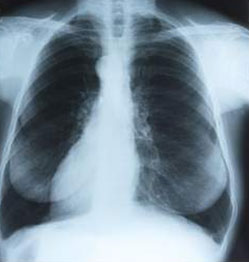

A Murky Picture of the Lungss

When autopsies were conducted on the bodies of those who smoked regularly, they brought to light the fact that a large number of air cavities in the lungs called alveoli had been destroyed. They also established that the color of the lungs was black as coal due to the presence of noxious chemicals from tobacco smoke.